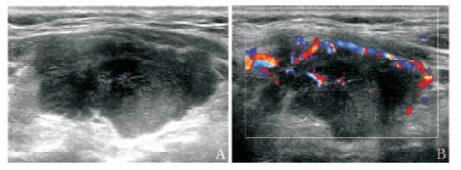

结果  CNB结果显示, 117例甲状腺病变中良性85例, 恶性28例, 可疑恶性2例, 取材不满意2例, 取材成功率98.3%;弥漫性病变37例, 甲状腺结节80例。29例手术患者术后病理显示恶性24例(22例乳头状癌, 2例淋巴瘤), 其中5例CNB为良性(假阴性); 良性5例。80例甲状腺结节中小于1 cm者2例, 1~2 cm者21例, 大于2 cm者57例。

Results  All patients completed CNB successfully and the satisfaction rate for tissue samples was 98.3%. The CNB pathologic results of 117 patients were as follows:85 cases were benign, 28 cases were malignant, 2 case were suspected malignant, and 2 cases were inadequate for diagnosis; 37 cases had diffuse lesions and 80 cases had nodules. In 29 patients (including 24 cases of malignancy and 5 cases of benign disease) who had undergone surgery, the CNB pathologic results in 5 cases were false negative compared with the pathologic results of surgery. The diameters of thyroid nodules were less than 1 cm in 2 cases, 1-2 cm in 21 cases, and more than 2 cm in 57 cases.